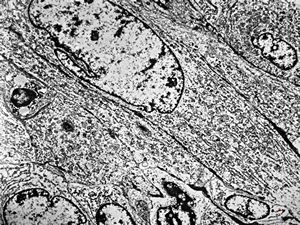

F,25y. | myopathy - atrophic and regenerating muscle cells